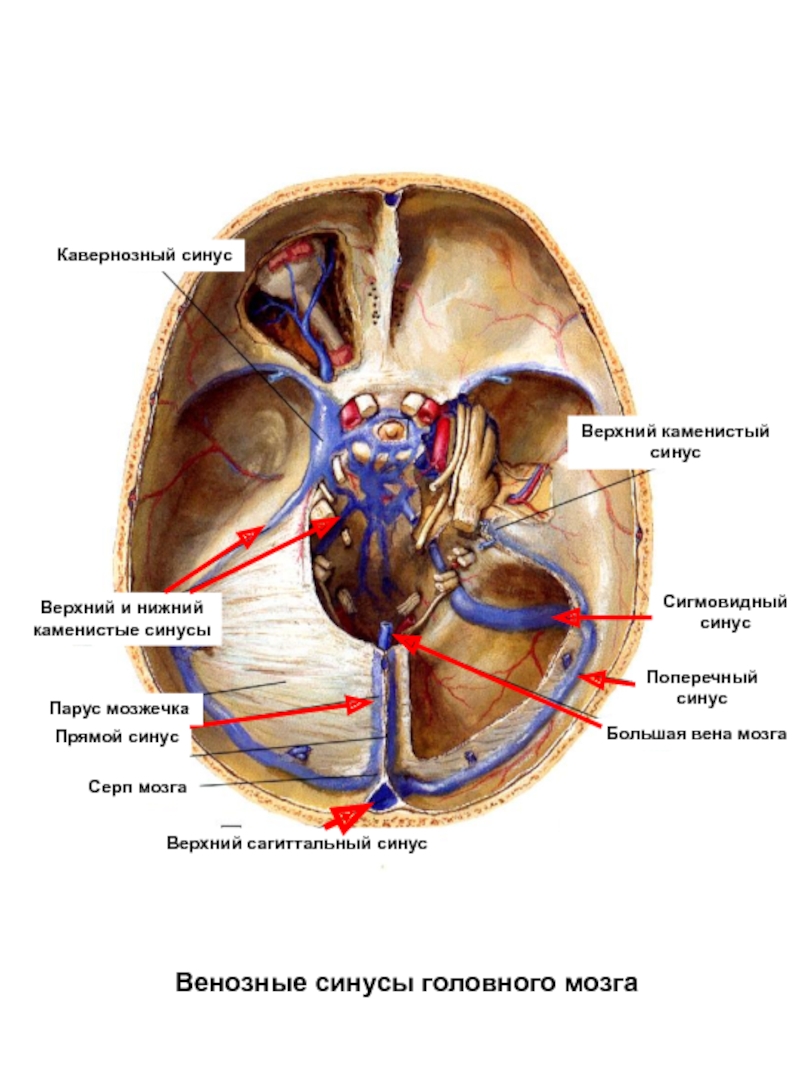

Анатомия внутренней яремной вены: КТ изображения